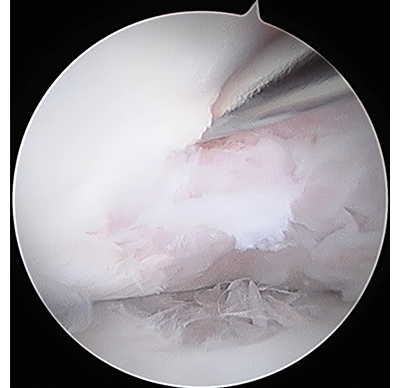

遊離体の摘出

内視鏡下の遊離体摘出や炎症組織である関節滑膜の切除を行います。

壊死を起こした病変部に対しては内視鏡下のドリリングや、内視鏡下あるいは直視下に骨軟骨柱や肋骨肋軟骨移植などを行います。